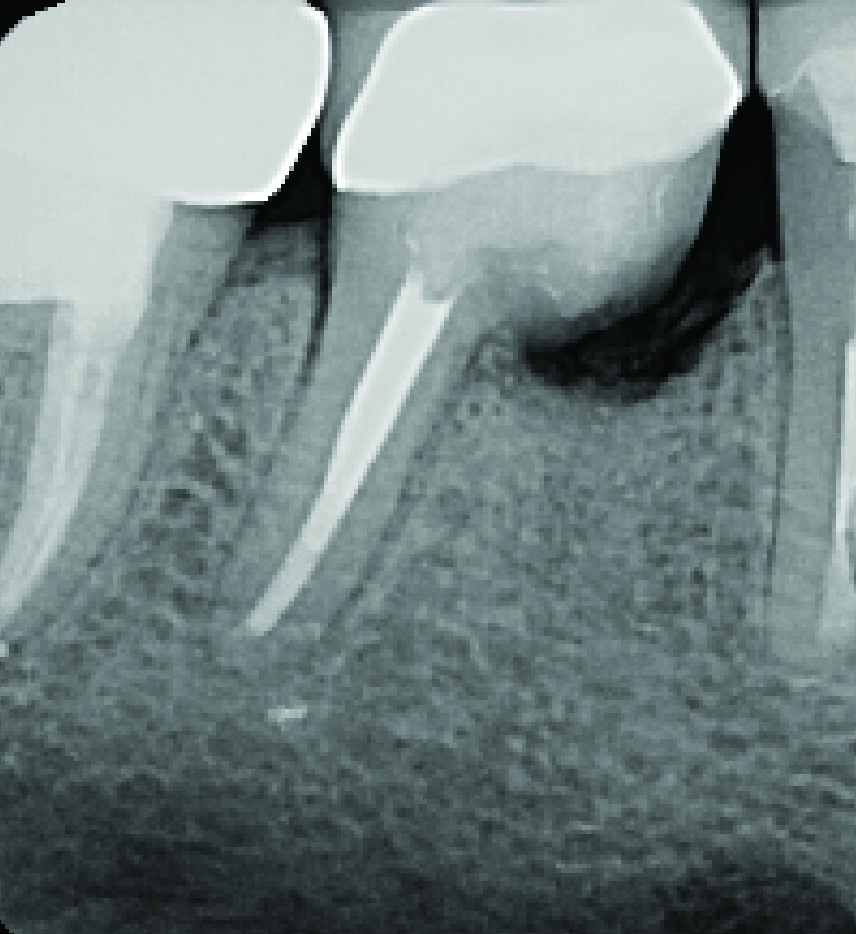

Fig 1 through Fig 4. Examples of multirooted teeth showing periradicular periodontitis and loss of periradicular bone support isolated to one root (indicated by red arrows). Fig 1: Tooth No. 3 distobuccal root with circumferential bone loss from the crestal bone height to the apex with stable mesiobuccal and palatal roots. Fig 2: Tooth No. 30 with a prior apical surgery showing bone loss surrounding a fractured mesial root. Fig 3: Tooth No. 19 with lateral and apical bone loss regions affecting a fractured mesial root. Fig 4: 3D CBCT imaging of tooth No. 3 depicting an apicomarginal bone loss defect affecting the mesiobuccal root with stable fused distobuccal and palatal roots.

Figure 3